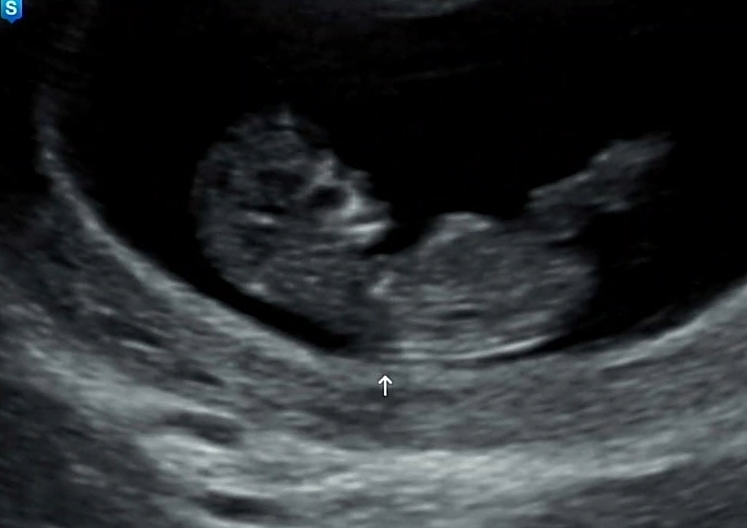

성별 아직 욕심이겠죠?ㅜㅜ

성별아직 기대하면 안되겠죠? 조금의 추측 부탁드려요..🤭 무증상이라 걱정했는데 별탈없이 잘 크고있대서 정말다행이에요ㅜㅜ